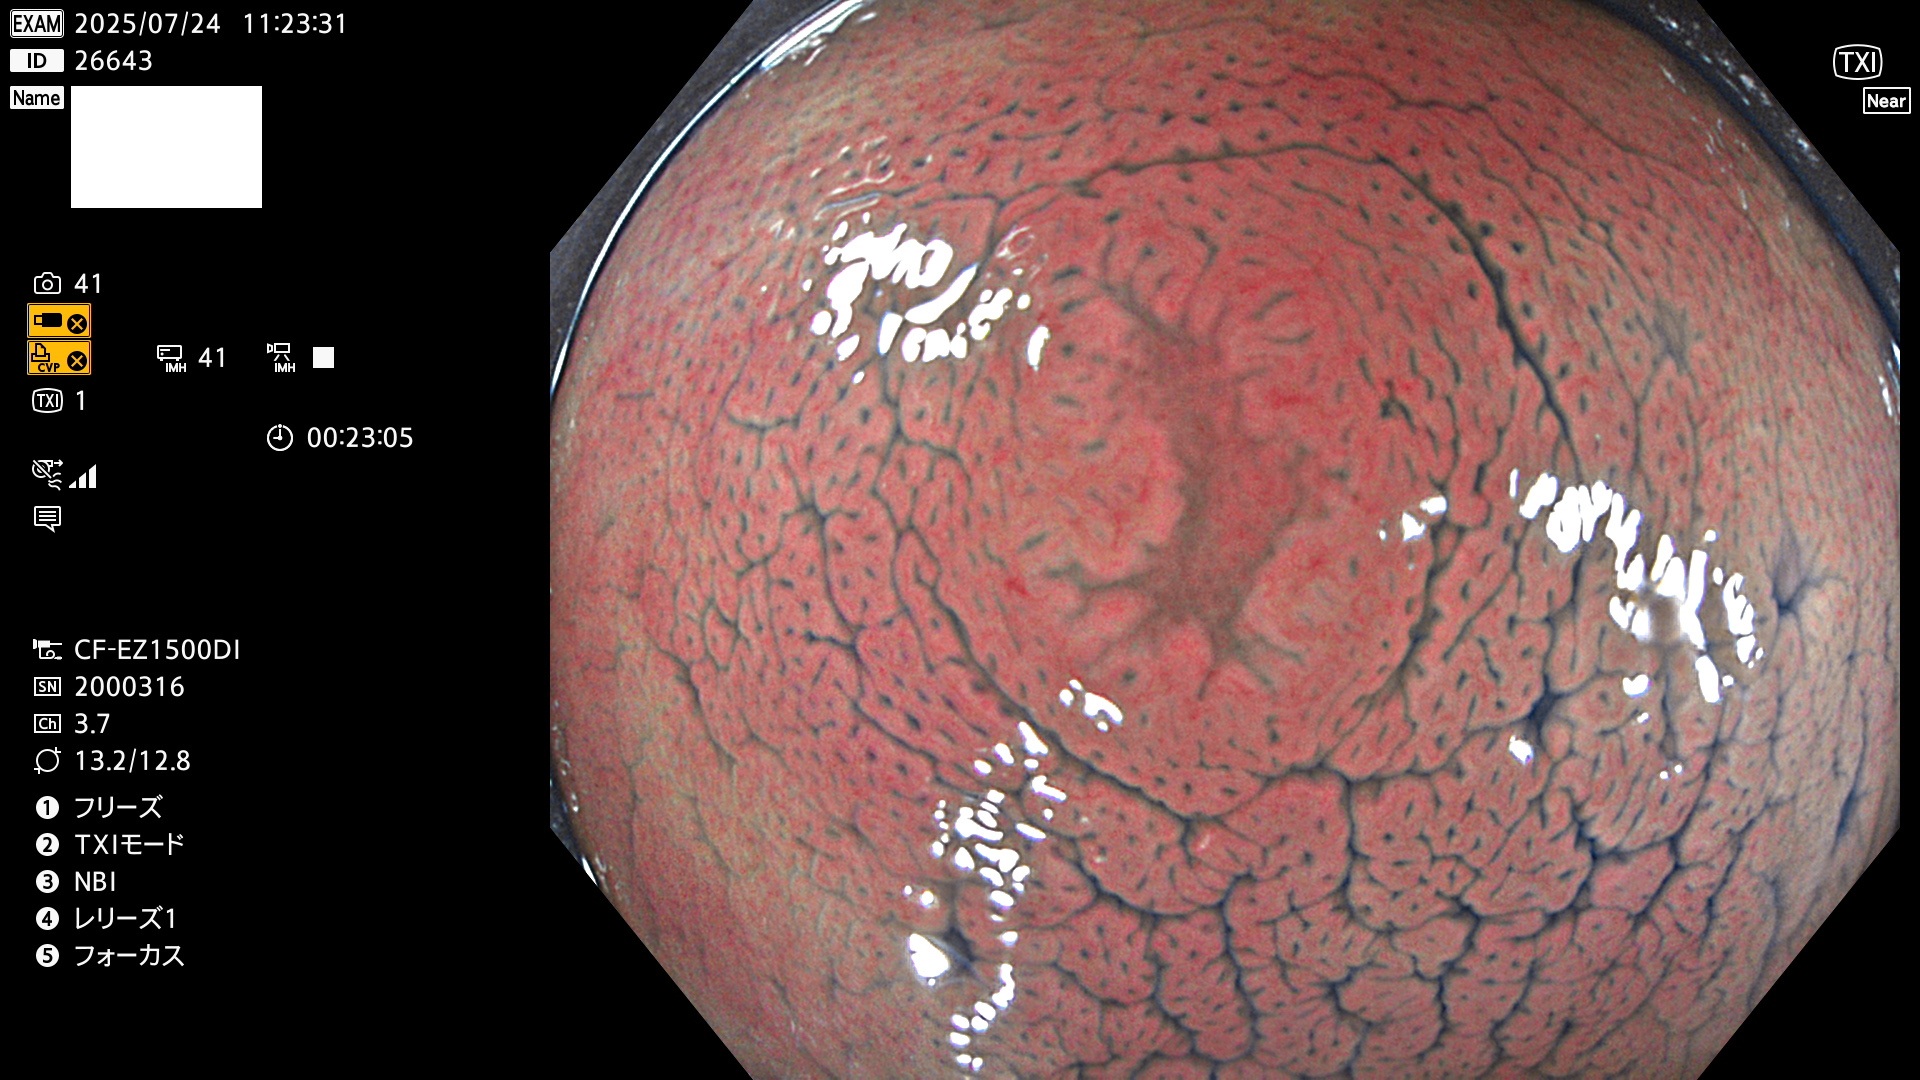

完全に平坦な物をUb、陥凹している物をUcと呼びます。Ubは認識が困難で、Ucはびらん(炎症)と紛らわしいために見落とされやすく、「内視鏡後・大腸癌」の原因になります。

専門的)何故、陥凹していると危険? 癌遺伝子の変異が蓄積すると細胞分裂が盛んになり隆起するのでは?と通常は思われるでしょう。しかし実際は逆です。これは2022年の記事にある「細胞はストレスに直面したら細胞分裂を止める(Dormancy 細胞老化に入り休眠する)という生命の基本的現象」によるものです(Oncogene Stress)。細胞老化を起こすのが癌抑制遺伝子で、この安全装置(ブレーキ)が壊れると癌になります(休眠からの覚醒)。ですから陥凹は「まだ癌では無いが癌化の直前」を意味します。特に「小サイズなのに陥凹している」病変は短期間に腫瘍進化(IntraTumor Heterogenity⇒2021年記事)が起きたことを意味します(=ゲノム不安定性)。

専門的)Uc=De Novo癌? 内視鏡の解像度が低かった時代、このような説もありました。しかし今日の高精度内視鏡では良性の微小なUc型腺腫(APC遺伝子異常の腺腫)が日常的に見つかります。Ucこそが多段階発癌(Adenoma-Carcinoma Sequence)のMain Routeです。

2025年7月24日〜7月27日の4日間(40件)15個 (Uc_ADR=15個/40人=38%)